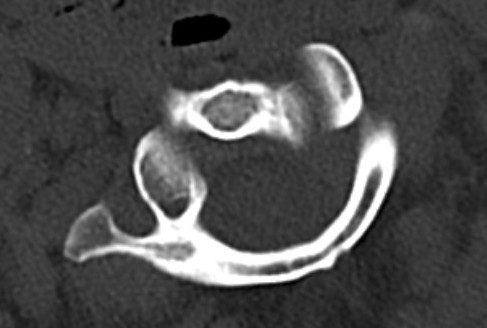

CT Scan

Atlanto-axial rotatory instability

Classification Fielding & Hawkins

| Type I |

Unilateral facet subluxation / dislocation ADI < 3 mm |

Transverse ligament intact | Most common |

| Type II |

Unilateral facet subluxation / dislocation Anterior displacement of the atlas by 3–5 mm ADI 3 - 5 mm |

Transverse ligament injury | |

| Type III |

Bilateral facet subluxation / dislocation Anterior displacement of atlas by more than 5 mm ADI > 5 mm |

Alar and tranverse ligament deficient Both lateral masses displaced anteriorly |

|

| Type IV | Posterior displacement of atlas | Ondontoid process deficient or fractured |

Rare Highest risk of neurological injury |